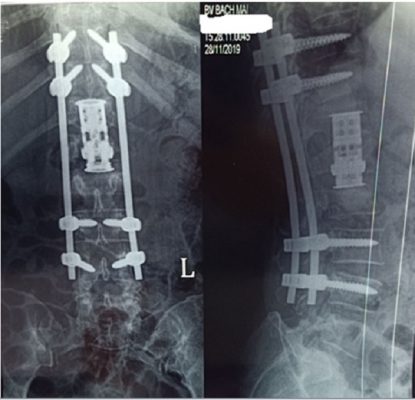

– Giải ép phía sau và cố định cột sống, ghép xương với xương tự thân.

– Cắt thân đốt sống /giải ép đường trước và cố định cột sống, ghép xương với xương tự thân,

– Cắt thân đốt sống /giải ép và cố định cột sống đường trước và phối hợp với cố định cột sống đường sau cùng lúc hoặc sau đó.

– Cố định cột sống đường sau, sau đó cắt thân đốt sống đường trước một thì hoặc 2 thì.